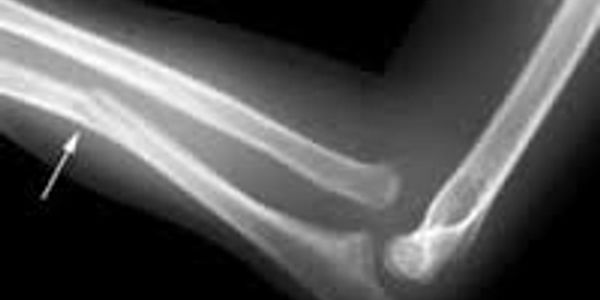

The most common fracture in a child or Infant is the green stick fracture. Imagine a young tree branch being bent the bark and inner wood would twist,bend but not break in two.

This principle applies to the young bone of a child. In many case it appears swollen, bruised and painful. The child can move it, however there are small hair line fractures along the bone